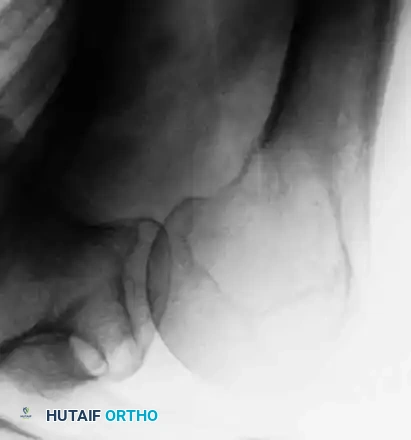

4. Curettage and Cementation of Distal Extremity Lesions

For lesions distal to the knee or elbow (e.g., distal tibia, ankle), where intramedullary nailing or massive endoprostheses are less feasible, extended curettage followed by defect packing with PMMA is highly effective. This technique provides immediate structural support and excellent pain relief.

Fig. 22-27: (A, B) Anteroposterior and lateral radiographs of the left ankle of a 78-year-old woman with metastatic kidney cancer. (C, D) Postoperative views after extended curettage and packing of the defect with methacrylate. The patient resumed immediate full weight-bearing with complete pain relief.